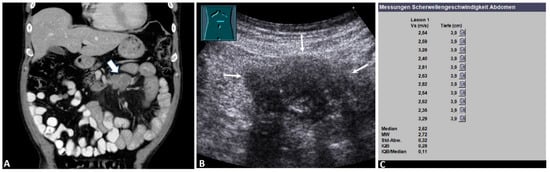

3.2. B-Mode Ultrasound Data

3.3. Acoustic Radiation Force Impulse Examinations